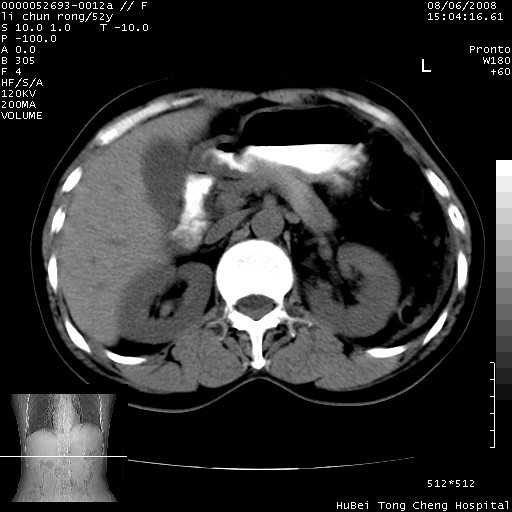

以下是引用云翔在2008-8-7 6:20:00的发言:[br]胰尾部囊性病变,考虑假囊肿,结合实验室检查疾病史

以下是引用zjzjr在2008-8-7 8:38:00的发言:[br]支持胰腺炎伴假囊肿形成,左肾小囊肿.少量腹水.

以下是引用随光逐影在2008-8-7 9:12:00的发言:[br]1)考虑胰腺炎伴假性囊肿形成可能性大;胰腺囊腺瘤待排。2)左肾小囊肿。3)少量腹水。